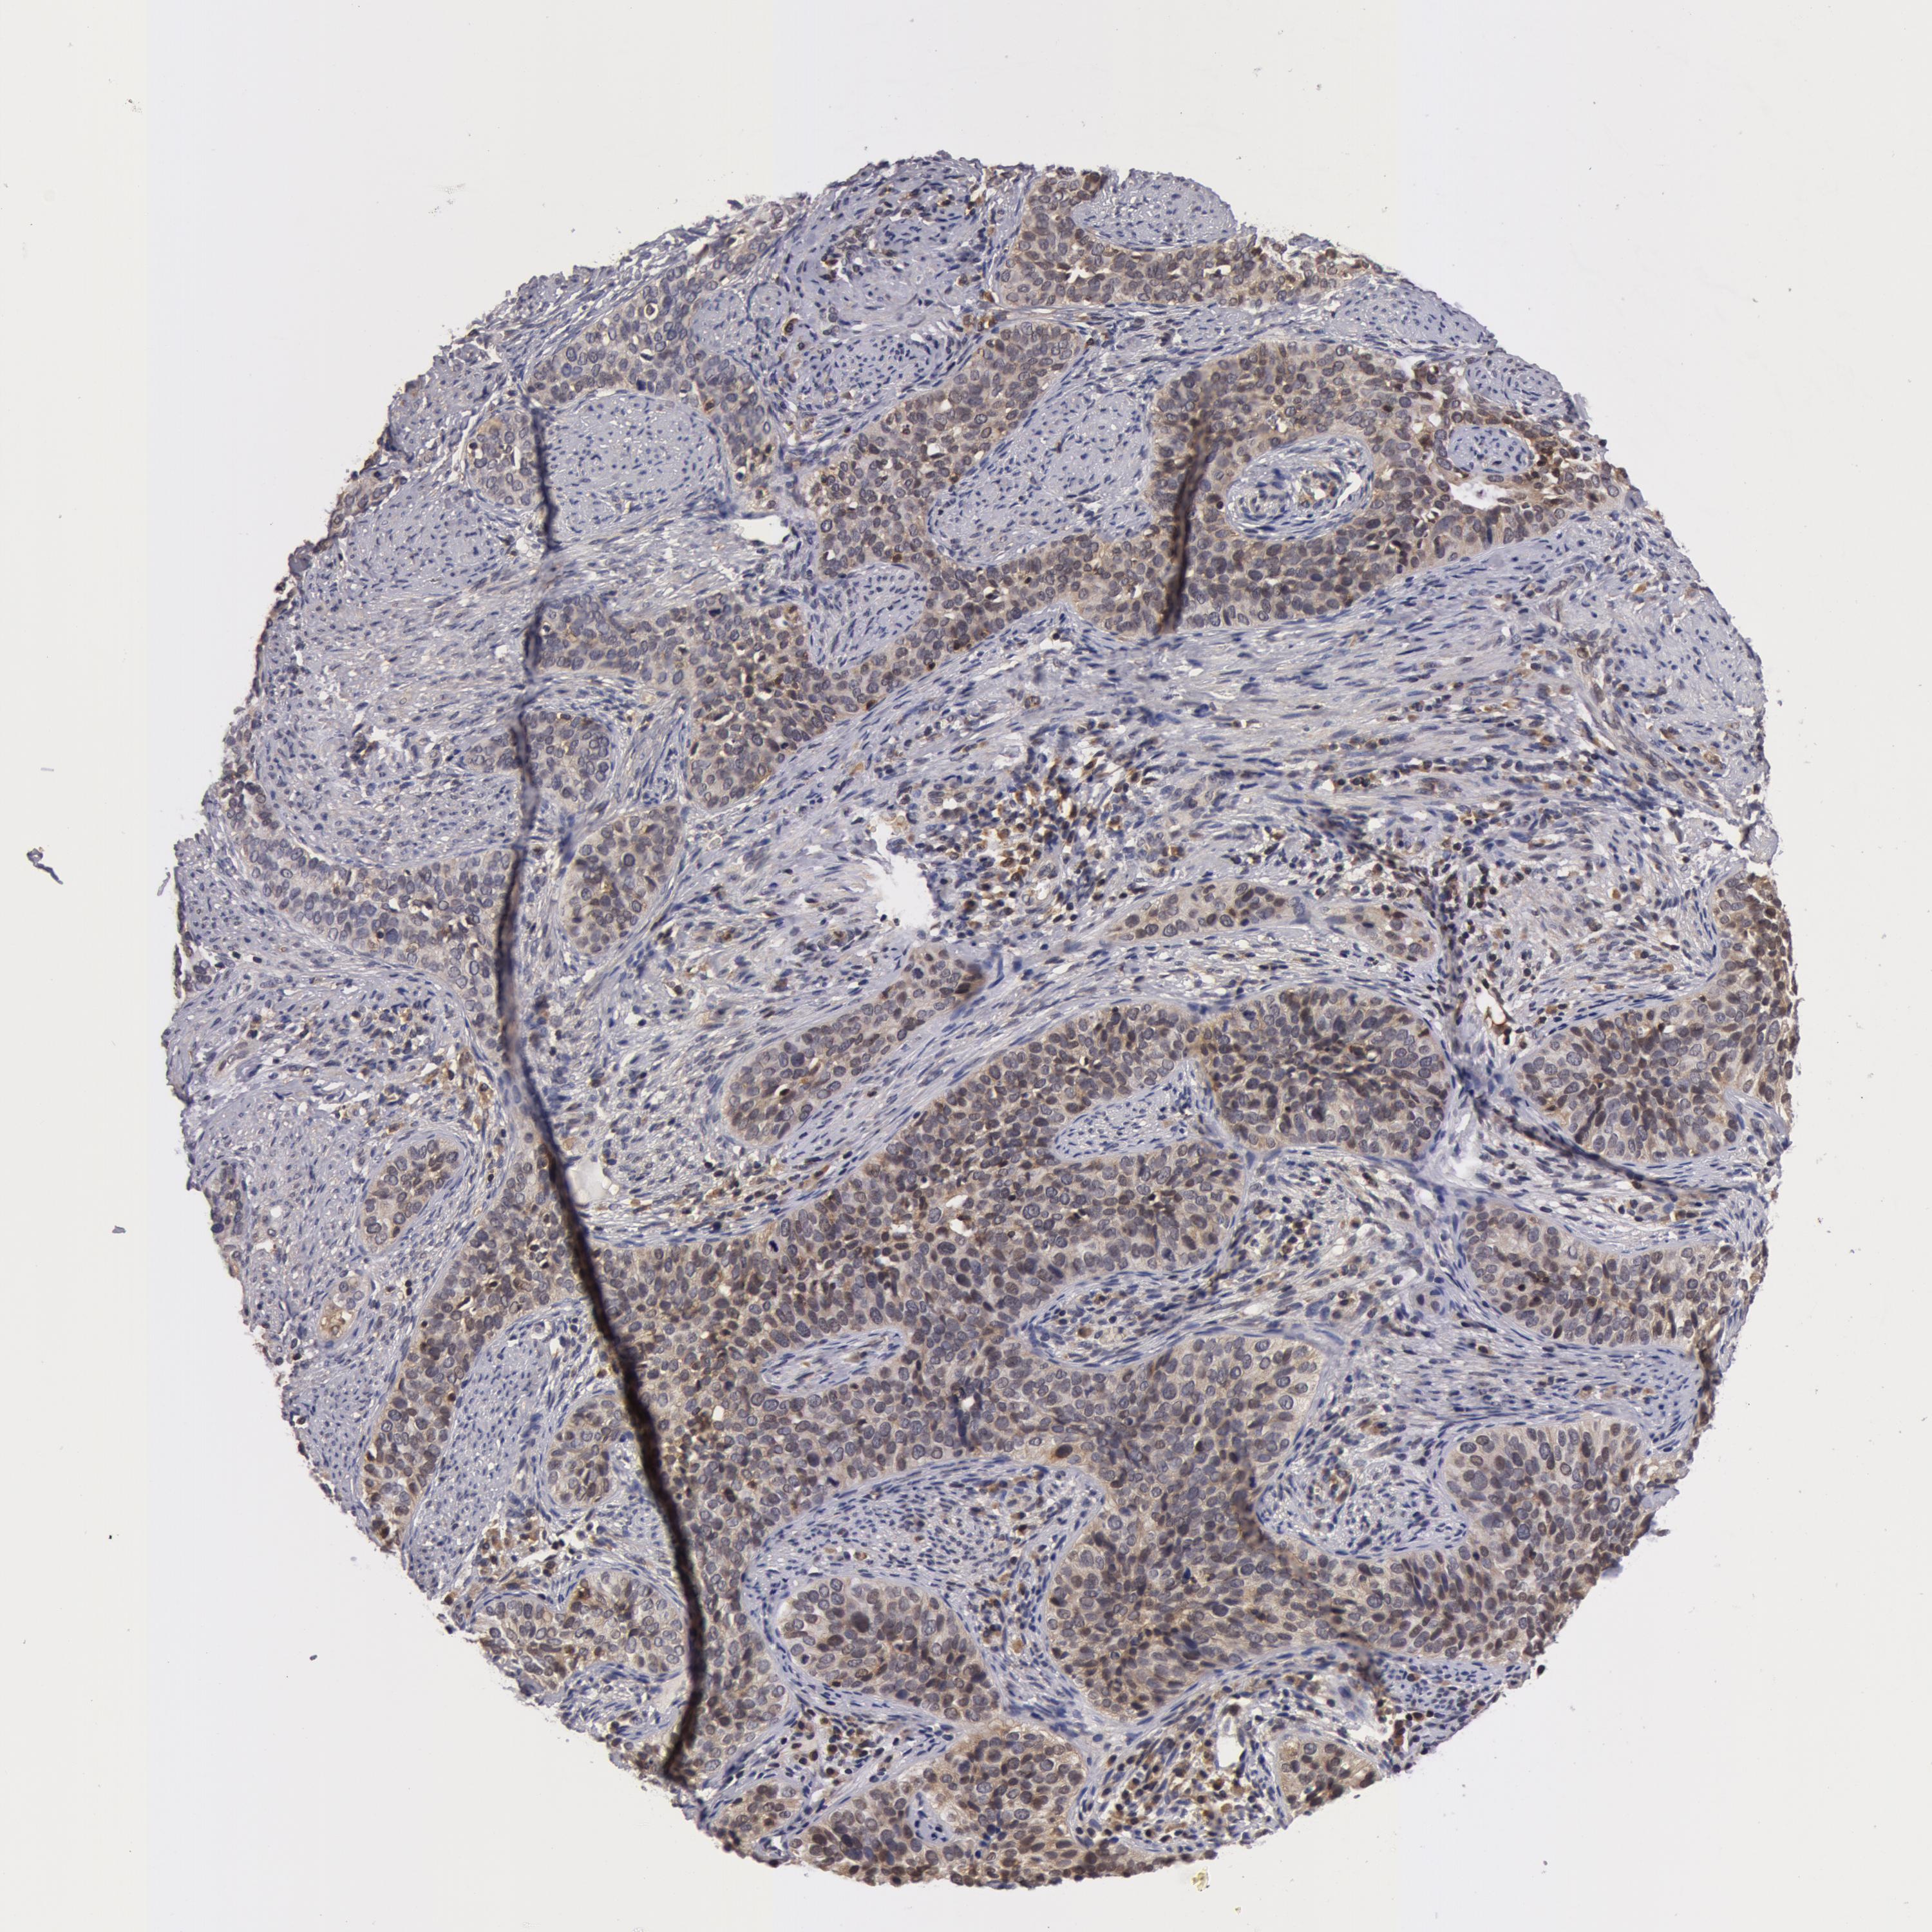

CERVICAL CANCER - Protein expressioni

A mouse-over function shows sample information and annotation data. Click on an image to view it in a full screen mode. Samples can be filtered based on level of antibody staining by selecting one or several of the following categories: high, medium, low and not detected. The assay and annotation is described here.

Note that samples used for immunohistochemistry by the Human Protein Atlas do not correspond to samples in the TCGA dataset.

Antibody stainingi

Antibody staining in the annotated cell types in the current human tissue is reported as not detected, low, medium, or high, based on conventional immunohistochemistry profiling in selected tissues. This score is based on the combination of the staining intensity and fraction of stained cells.

Each image is clickable and will lead to virtual microscopy that enables deeper exploration of all samples and also displays staining intensity scores, fraction scores and subcellular localization as well as patient and tissue information for each sample.

Antibody HPA001521

Staining

High

Medium

Low

Not detected

Intensity

Strong

Moderate

Weak

Negative

Quantity

>75%

75%-25%

<25%

None

Location

Nuclear

Cytoplasmic/membranous

Cytoplasmic/membranous,nuclear

Squamous cell carcinoma, NOS